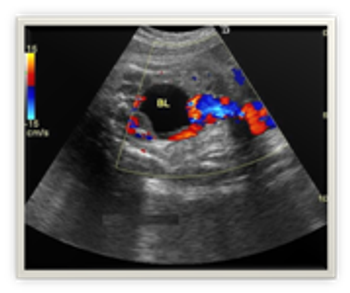

Postabortal placental polyps and uterine arteriovenous malformations can look identical on ultrasonography. Read how saline instillation sonohysterography helped discern the diagnosis.